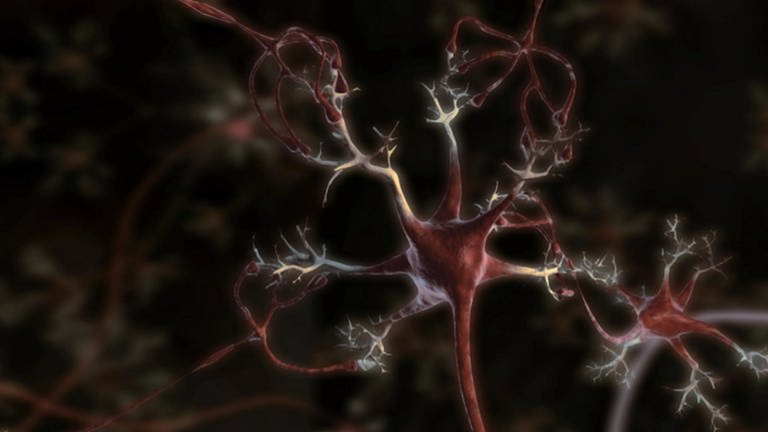

Wenn ein Virus in die Zelle eindringt, zwingt es sie komplett unter seine Herrschaft. Alle ihre Funktionen werden auf eine einzige Aufgabe reduziert: die Produktion von immer mehr Kopien des Virus. Letztlich gehen der Zelle dabei sämtliche Energie und das Baumaterial aus, sie verhungert regelrecht. Kurz bevor es so weit ist, aktiviert sie den Selbstzerstörungsmechanismus. Lennart Nilsson versucht, mit seinen Fotos zu einem besseren Verständnis des Ablaufs einer Virus-Infektion beizutragen. Ergänzende Computeranimationen veranschaulichen, wie das Leben in der Zelle funktioniert – und in welcher Katastrophe es endet, wenn Viren ihr zerstörerisches Werk vollenden.